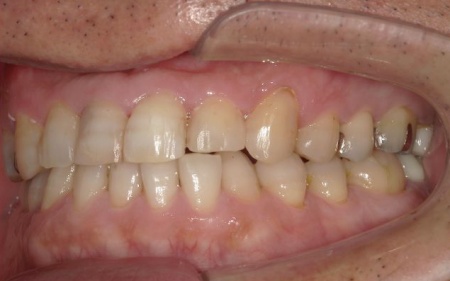

40代男性 虫歯治療やインプラント治療で口腔内全体を修復したあと部分矯正で噛み合わせを改善した症例

前歯の反対咬合については、部分矯正で改善を図ります。

前歯の噛み合わせ治療では、上顎の内側に歯を内側から動かす装置「リンガルアーチ」を装着します。併せて、上前歯の表面に「ブラケット」と呼ばれるボタン状の装置を接着し、そこにワイヤーを通して歯を動かす「マルチブラケット装置」を用いて部分矯正を行いました。

最後に、噛み合わせが改善していること、インプラントや被せ物に痛みや違和感がないことなどを確認し、治療を終了しています。